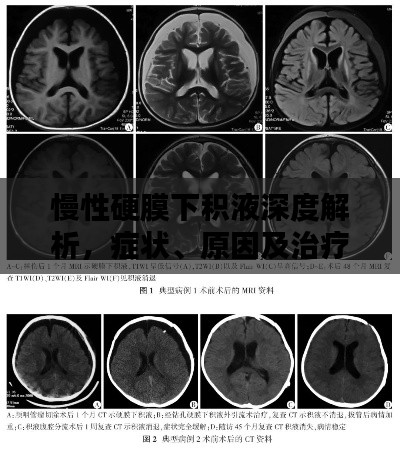

诊断与治疗

对于慢性硬膜下积液的诊断,通常需要进行头颅CT或MRI等影像学检查,治疗方法主要包括药物治疗和手术治疗,药物治疗主要是对症治疗,如使用脱水药物降低颅内压等,对于严重的慢性硬膜下积液,可能需要手术治疗以消除积液并恢复颅内压力平衡。